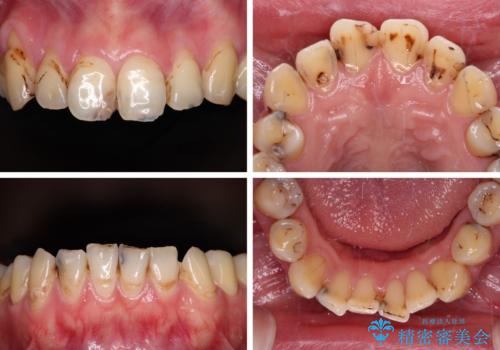

- 上下前歯や奥歯の虫歯治療を希望して来院された患者様です。

全顎的にむし歯が多く、根管治療の必要奥歯や、審美的に気になっている前歯を中心にオールセラミッククラウンにて補綴治療を行うこととしました。

上顎前歯は歯肉退縮により歯根が露出していたため、事前に歯肉移植術により根面被覆を行い、その後にオールセラミッククラウンを装着することとしました。

歯肉移植術による根面被覆を行うかどうかは非常に悩まれていましたが、歯肉が覆われたことで長く見えていた歯の長さが整い、きれいな前歯の仕上がりとなりました。